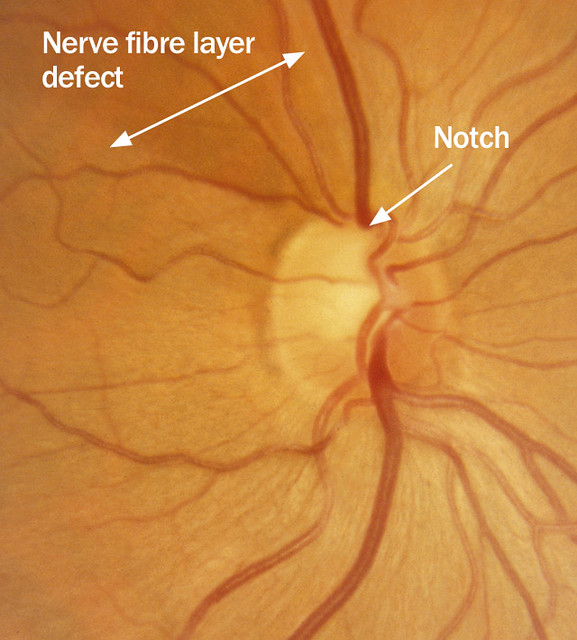

Атрофия зрительного нерва Лебера: Симптомы и лечение